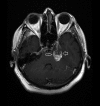

Case report: In this report we describe a patient complaining of vertigo caused by spontaneous rupture of dermoid cyst, preoperatively diagnosed by CT and MRI. Cranial CT revealed a dense fatty lesion adjacent to the posterolateral parasellar region on the left with multiple small, dense fat droplets scattered in the subarachnoid space corresponding to a dermoid cyst rupture. Cranial MRI sections revealed a lesion with mixed-signal-intensity and multiple hyperintense droplets scattered through the cerebellar surface on the left. No enhancement was found on axial T1-weighted MRI after intravenous Gadolinium administration. Diffusion weighted image (DWI) and apparent diffusion coefficient map studies exhibited explicit restricted diffusion.